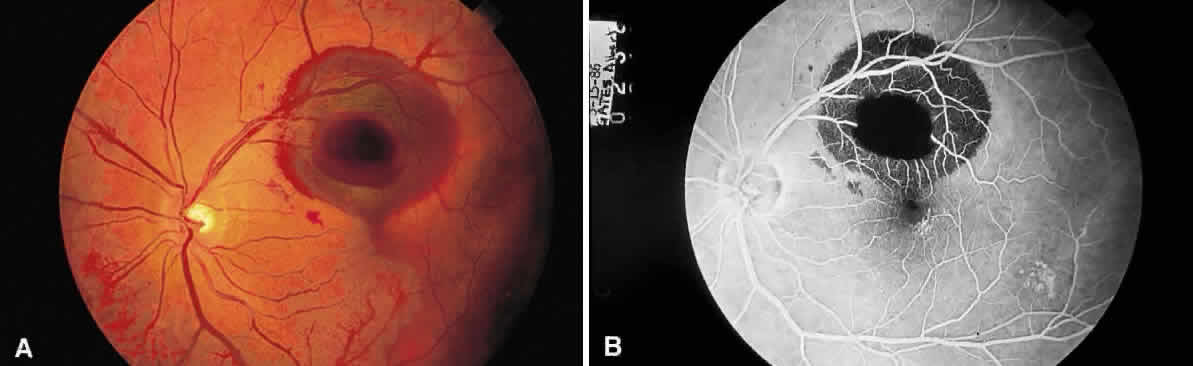

Fig. 13. A. Fundus photograph of a subpigment epithelium hemorrhage superotemporal

to the disc secondary to a macroaneurysm. Notice its dark color and sharp

border. The central portion of the hemorrhage has extended through

the sensory retinal to the subinternal limiting membrane area. B. Fluorescein angiography showing the retinal vessels overlying the deep

hemorrhage but obscured by the central extension anteriorly. (B, courtesy of William Tasman, MD, Philadelphia, PA) Fig. 13. A. Fundus photograph of a subpigment epithelium hemorrhage superotemporal

to the disc secondary to a macroaneurysm. Notice its dark color and sharp

border. The central portion of the hemorrhage has extended through

the sensory retinal to the subinternal limiting membrane area. B. Fluorescein angiography showing the retinal vessels overlying the deep

hemorrhage but obscured by the central extension anteriorly. (B, courtesy of William Tasman, MD, Philadelphia, PA)

|